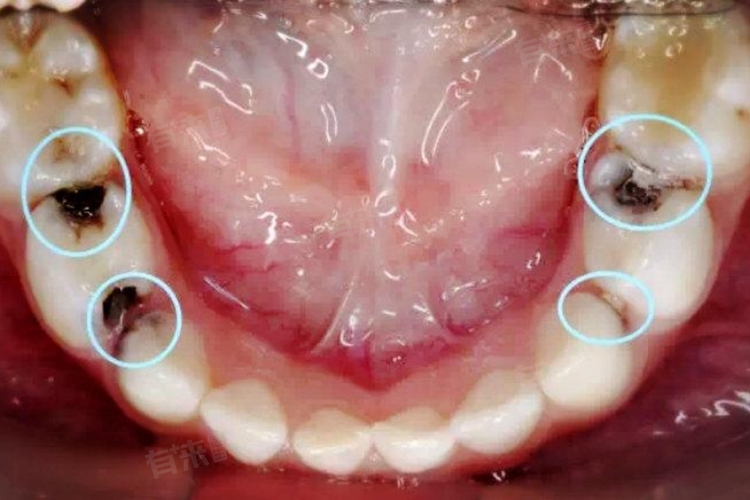

2、邻面龋齿:牙齿邻接面发生龋坏时,早期可能表现为边缘透黑的色泽改变。这种黑色通常不均匀,随着龋坏加深会形成明显的龋洞。邻面龋初期不易察觉,需通过X光片检查确诊。

牙齿边缘出现黑色现象是常见的口腔问题,主要与外在色素沉积和牙齿本身病变有关。从口腔医学角度分析,常见原因外源性色素沉积、邻面龋齿、牙结石堆积、牙齿内部变色等。